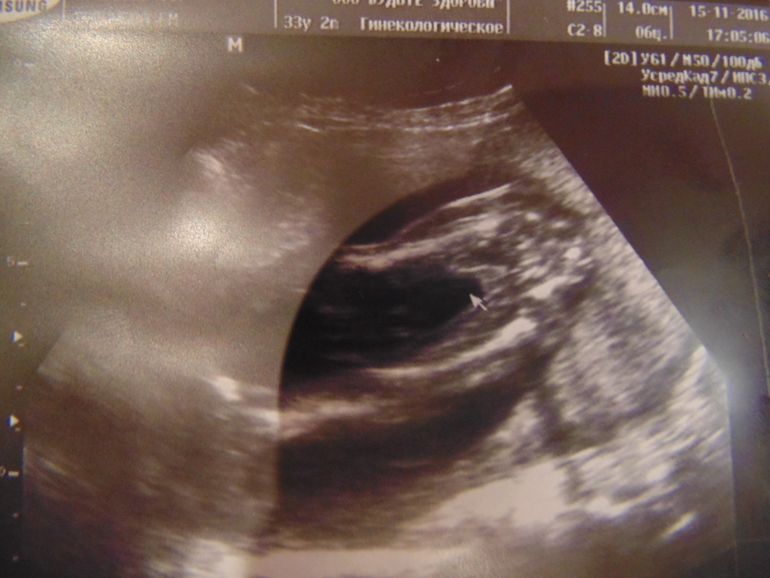

Изображение

14.02.2024

Анна, оххх темку вы старую открыли) моей с узи девочке уже 6,5 лет )) Вас поздравляю с Б😊